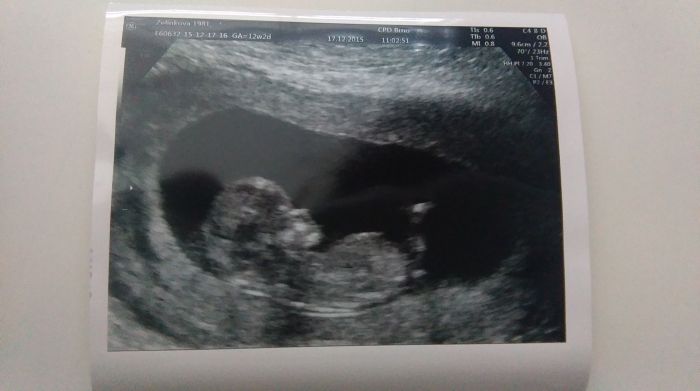

přikládám fotečku

Akorát mě soupl o týden datum porodu nikdy sem neměla žádného obrika tak i tentokrát jsme o týden mladší :) takže ne 29.6. Ale 2.7.